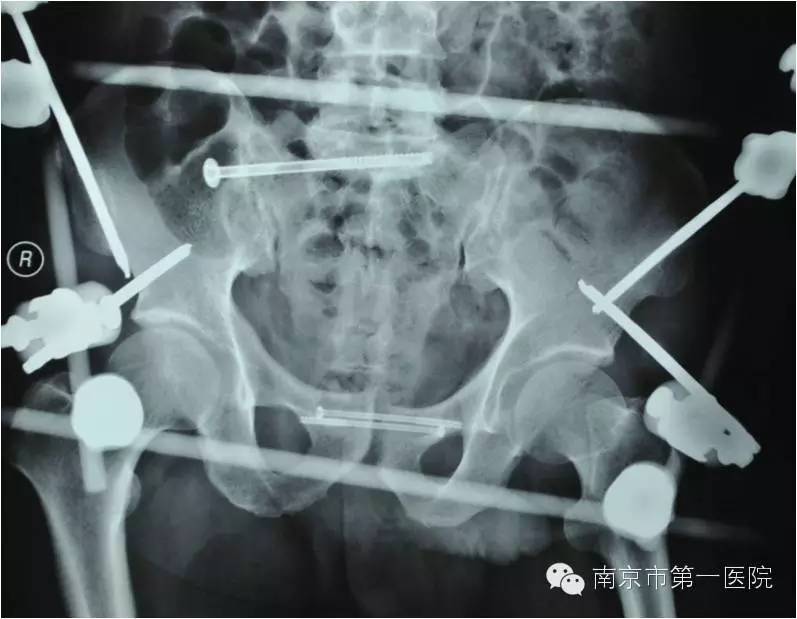

我院骨科行家梁斌接到通知后,开通多发伤绿色通道,迅速召集科内骨干医生进行术前讨论、制定手术计划。斟酌到患者创伤严重、出血量大,必须最大程度地减少手术伤口,梁主任决定立刻采取微创技术进行骨盆闭合复位支架外固定术。

术中,主刀医生操作技术娴熟,争分夺秒,有条不紊地进行着各项操作。经过1个小时,手术顺利结束,告捷修复了患者重度骨折的骨盆。据悉,整个手术过程中,创伤小、出血量低,切口大小也仅有1-2cm左右。